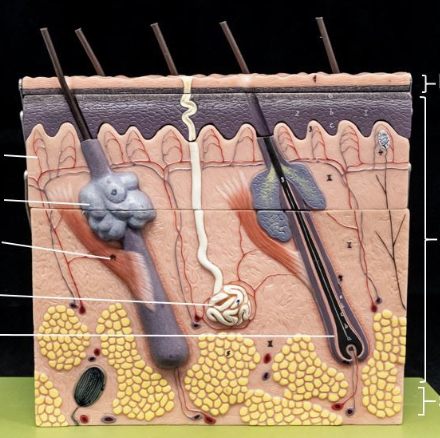

Label

2